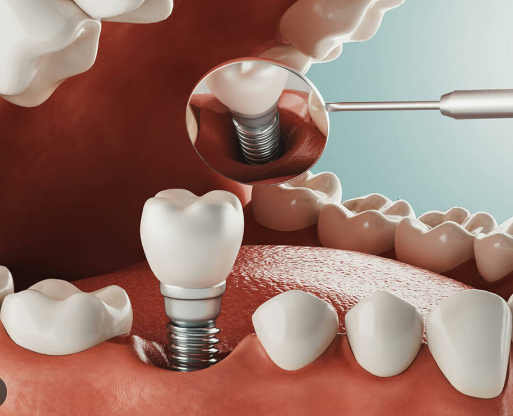

원데이 임플란트에 대해 찾으셨나요? 그래서 오늘 원데이 임플란트 비용 및 가격, 조건, 추천 대상 들에 대해 살펴보겠습니다. 오늘 내용을 확인하시면 원데이가 어떤 차이점을 가지고 있는지, 어느 대상에게 적합한지, 가격 및 장단점 등에 대해서 정리가 되실 것입니다. 하기를 참고해주세요. 근처 임플란트 가격 조회 🔍 원데이 임플란트 원데이 임플란트는 이름 그대로 하루 만에 임플란트 시술이 … Read more